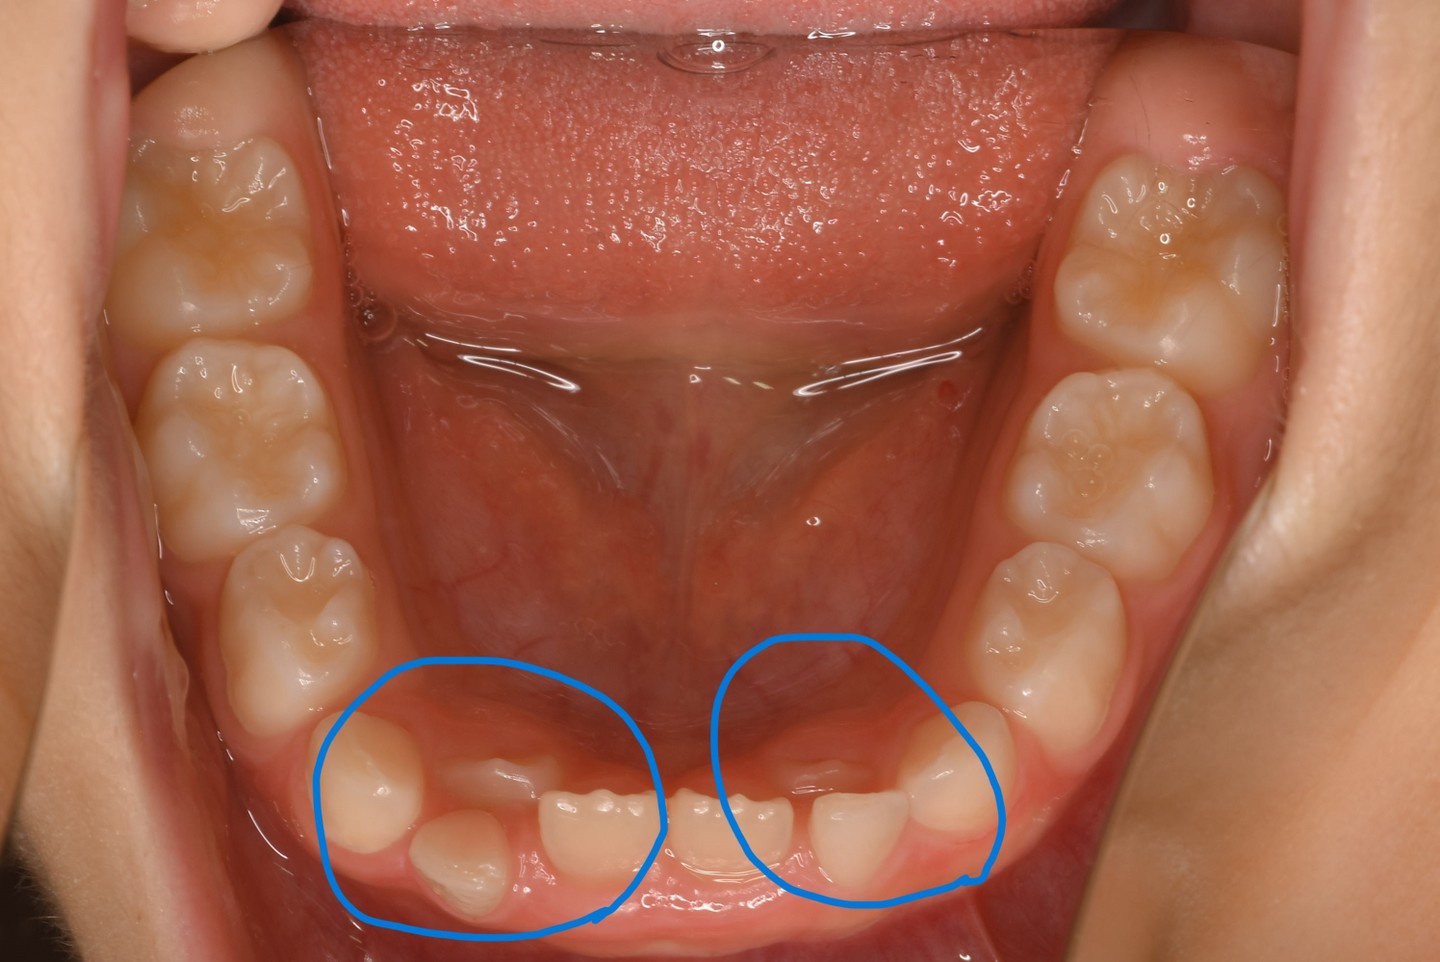

乳歯が抜ける前に永久歯が生えてきた!

お子さんの乳歯が抜けないうちに永久歯が生えてきたとき、歯医者さんにみてもらおう!と親御さんが連れて来てくださいます。

①永久歯が生えて来て、乳歯と同じくらいの背の高さなのに自然に抜けないとき。